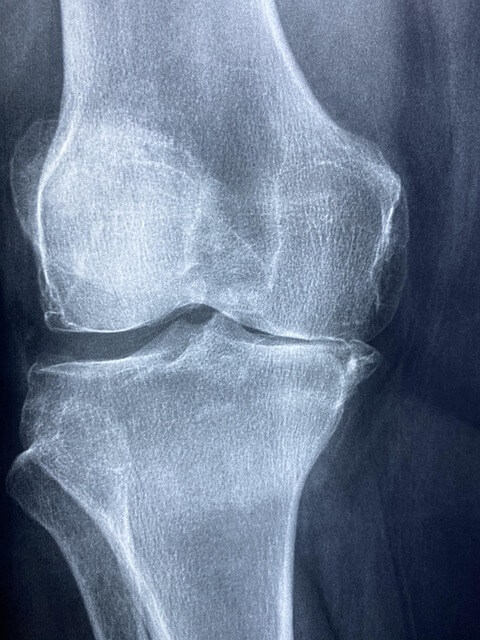

관절염은 한 번 생기면 완치가 어려운 만성 질환입니다. 하지만 평소 생활 속에서 관절에 무리가 가지 않는 운동을 꾸준히 실천하면 예방에 큰 도움이 됩니다. 특히, 관절 주변의 근육을 강화하고 유연성을 높여주는 운동은 관절염 예방뿐 아니라 삶의 질 향상에도 긍정적인 영향을 줍니다.

그렇다면 어떤 운동이 효과적일까요? 전문가와 보건기관이 추천하는 관절에 좋은 운동법을 소개합니다.